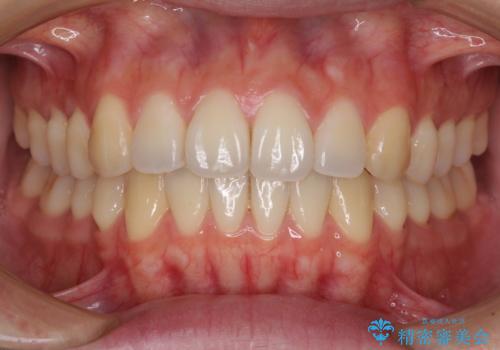

オープンバイトでかみにくい インビザラインによる矯正治療

- 前歯の上下スペースによる食べにくさを気にして来院された患者様です。

インビザラインにより上下の前歯の隙間を閉じていくこととしました。

上下の奥歯を圧下させるようにすることで、前歯を接触させるように計画しました。

上下の隙間に舌が入り込むことがオープンバイトの原因であったため、舌の筋肉のトレーニングも並行して行い、後戻りの抑制を図りました。